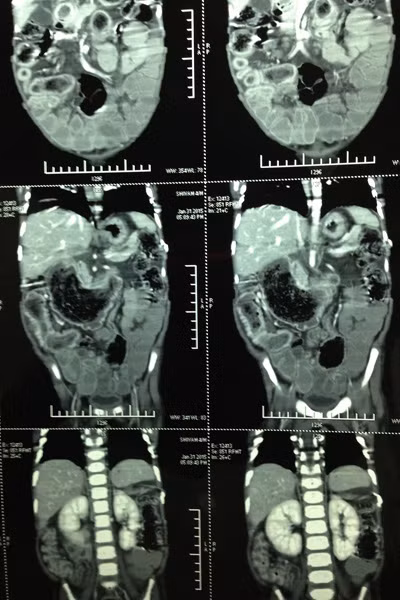

Cha của bé, ông Sunil Kumar, 36 tuổi, nói: "Con tôi khóc cả ngày và làm cách nào bé cũng không ngừng khóc. Chúng tôi đã đưa con đến gặp bác sỹ nhưng họ không thể chẩn đoán ra bệnh”. Thậm chí, một bác sỹ gần nhà đã nói bé bị nhiễm trùng dạ dày và kê đơn uống thuốc. Sau đó, bụng của bé phình ra bất thường. Cuối cùng, tiến sỹ y khoa Shilpa Sharma đã cho chụp CT và phát hiện một búi tóc lớn trong dạ dày bé. Họ đã không thể tin được, búi tóc dài hơn 1,2m.